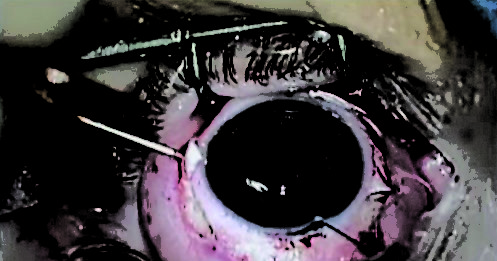

Cataratta in presenza di IOL-fachiche

1 Osservazione ed anamnesi

La paziente, di sesso femminile, si reca per la prima volta nel nostro studio...